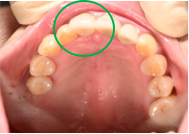

虫歯の治療をするときに、銀歯や白いかぶせ物をすることがありますが、細菌がつきやすい素材とつきにくい素材があることをご存知ですか?患者さんのお口の中を見ますと、銀歯や保険のプラスチック製の白いかぶせ物にはプラーク(歯垢:細菌のかたまり)がたくさんついていますが、陶器製の『オールセラミック』の被せものには、プラークがほとんどついていません。

銀歯やプラスチックは、お口の中で酸化、劣化したり細かい傷がついたりして、表面にプラークがつきやすくなります。プラークの中に棲みついている虫歯菌は虫歯の再発(2次カリエス)を引き起こし、歯周病菌は歯ぐきに炎症を起こして歯周病を引き起こします。

一方、オールセラミックはほとんど劣化しませんし、表面に傷もつきにくいので、プラークがつきにくい状態が保てます。虫歯の再発や歯周病になるリスクも、その分減ります。